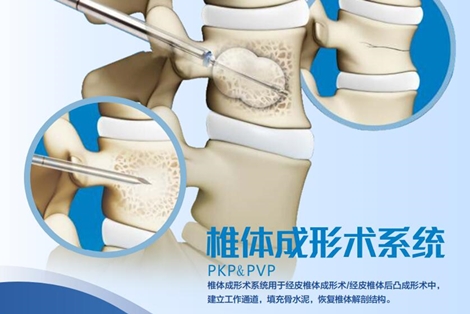

椎體成形術系統 (PKP&PVP)宣傳彩頁

發布時間:2020-08-25